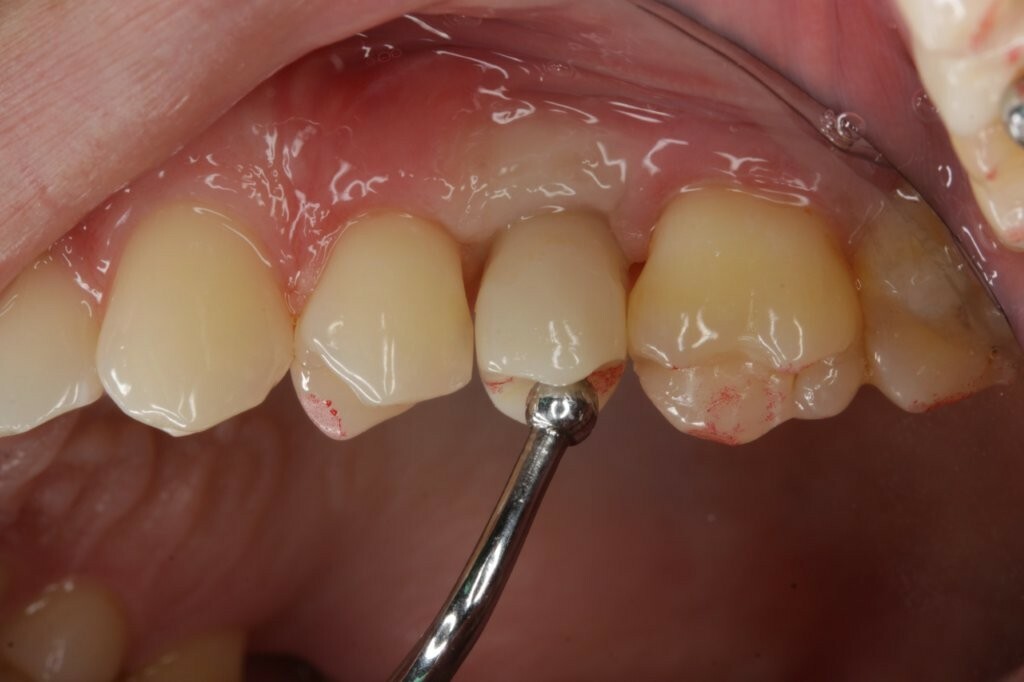

Im Mund wurde zunächst der Gingivaformer entfernt. Die Durchtrittsöffnung wurde mit Chlorhexidin (CHX) gereinigt, und das Implantat mit CHX-Gel zum Verbleib gefüllt. Danach wurde die Hybrid-Abutmentkrone behutsam in das Implantat eingesetzt. Aufgrund ihrer größeren Dimension verdrängte die Hybrid-Abutmentkrone das Zahnfleisch. Nachdem die definitive Position erreicht war und die Abutmentschraube mit einem Drehmoment von 20 Ncm angezogen wurde, wurden die Approximalkontakte mit Zahnseide und die Okklusion mit Okklusionsfolie überprüft (Abb. 28-30). Dank der hervorragenden Passung konnte der Schraubenkanal verschlossen werden. Dafür wurde die Abutmentschraube mit sterilisiertem Teflon-Band abgedeckt (Abb. 31) und dieses fest komprimiert, sodass eine verbleibende Kavität von ca. 2,5-3 mm Tiefe entstand. Dies verhindert das Eindringen von Adhäsiv und Verschluss-Composite in den Schraubenantrieb, was eine einfache und sichere Entnahme der Krone im Falle einer Revision ermöglicht.